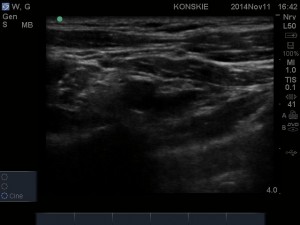

Wykorzystując dostęp LSICA liniową głowicę USG (u osób otyłych lub silnie umięśnionych konieczne będzie użycie głowicy convex) przykładamy w płaszczyźnie strzałkowej, tuż poniżej obojczyka i bezpośrednio przyśrodkowo w stosunku do wyrostka kruczego łopatki. W obrazie USG widzimy dwie warstwy mięśni: powierzchownie mięsień piersiowy większy, poniżej mięsień piersiowy mniejszy. Bezpośrednio poniżej mięśnia piersiowego mniejszego i jego powięzi (hiperechogeniczna linijna struktura) odnajdujemy naczynia pachowe (żyła pachowa, ulegająca kompresji leży zwykle poniżej tętnicy). Najczęściej na głębokości 3-5 cm, możemy rozróżnić trzy hiperechogeniczne pęczki splotu ramiennego ułożone wokół tętnicy pachowej: pęczek boczny, przyśrodkowy i tylny. Ułożenie pęczków względem naczynia jest bardzo zmienne osobniczo (patrz schemat ponizej), lecz najczęściej pęczek boczny leży dogłowowo w stosunku do tętnicy (pomiędzy godziną 9 a 12), pęczek przyśrodkowy doogonowo (pomiedzy 3 a 6 godziną) a pęczek tylny do tyłu od tętnicy ( pomiędzy 6 a 9 godziną). Głębiej w stosunku do struktur naczyniowo-nerwowych możemy uwidocznić opłucną oraz cień żebra. Należy pamiętać, iż poszczególne struktury nerwowe ulegają znacznemu przemieszczeniu podczas odwodzenia znieczulanej kończyny. Odwodząc kończynę pod kątem 90 stopni pęczki zbliżają się do siebie oraz przemieszczają się w stronę dogłowową.

- Sonoanatomia splotu ramiennego – dostęp LSICA